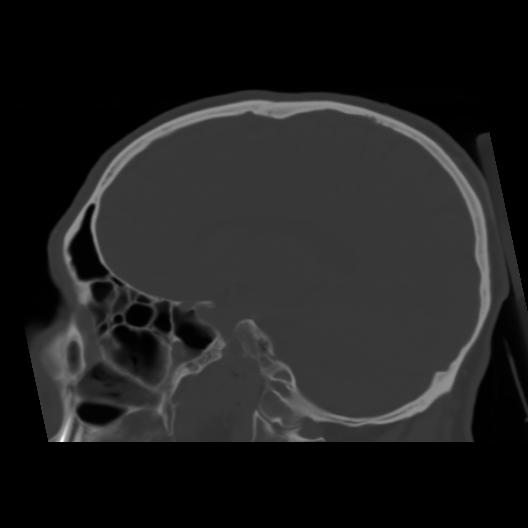

6 CEREBRO,,Sagittal,3.000,CEREBRO,Sagittal,